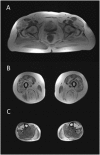

Congenital myasthenic syndromes are inherited disorders that arise from impaired signal transmission at the neuromuscular junction. Mutations in at least 20 genes are known to lead to the onset of these conditions. Four of these, ALG2, ALG14, DPAGT1 and GFPT1, are involved in glycosylation. Here we identify a fifth glycosylation gene, GMPPB, where mutations cause congenital myasthenic syndrome. First, we identified recessive mutations in seven cases from five kinships defined as congenital myasthenic syndrome using decrement of compound muscle action potentials on repetitive nerve stimulation on electromyography. The mutations were present through the length of the GMPPB, and segregation, in silico analysis, exon trapping, cell transfection followed by western blots and immunostaining were used to determine pathogenicity. GMPPB congenital myasthenic syndrome cases show clinical features characteristic of congenital myasthenic syndrome subtypes that are due to defective glycosylation, with variable weakness of proximal limb muscle groups while facial and eye muscles are largely spared. However, patients with GMPPB congenital myasthenic syndrome had more prominent myopathic features that were detectable on muscle biopsies, electromyography, muscle magnetic resonance imaging, and through elevated serum creatine kinase levels. Mutations in GMPPB have recently been reported to lead to the onset of muscular dystrophy dystroglycanopathy. Analysis of four additional GMPPB-associated muscular dystrophy dystroglycanopathy cases by electromyography found that a defective neuromuscular junction component is not always present. Thus, we find mutations in GMPPB can lead to a wide spectrum of clinical features where deficit in neuromuscular transmission is the major component in a subset of cases. Clinical recognition of GMPPB-associated congenital myasthenic syndrome may be complicated by the presence of myopathic features, but correct diagnosis is important because affected individuals can respond to appropriate treatments.